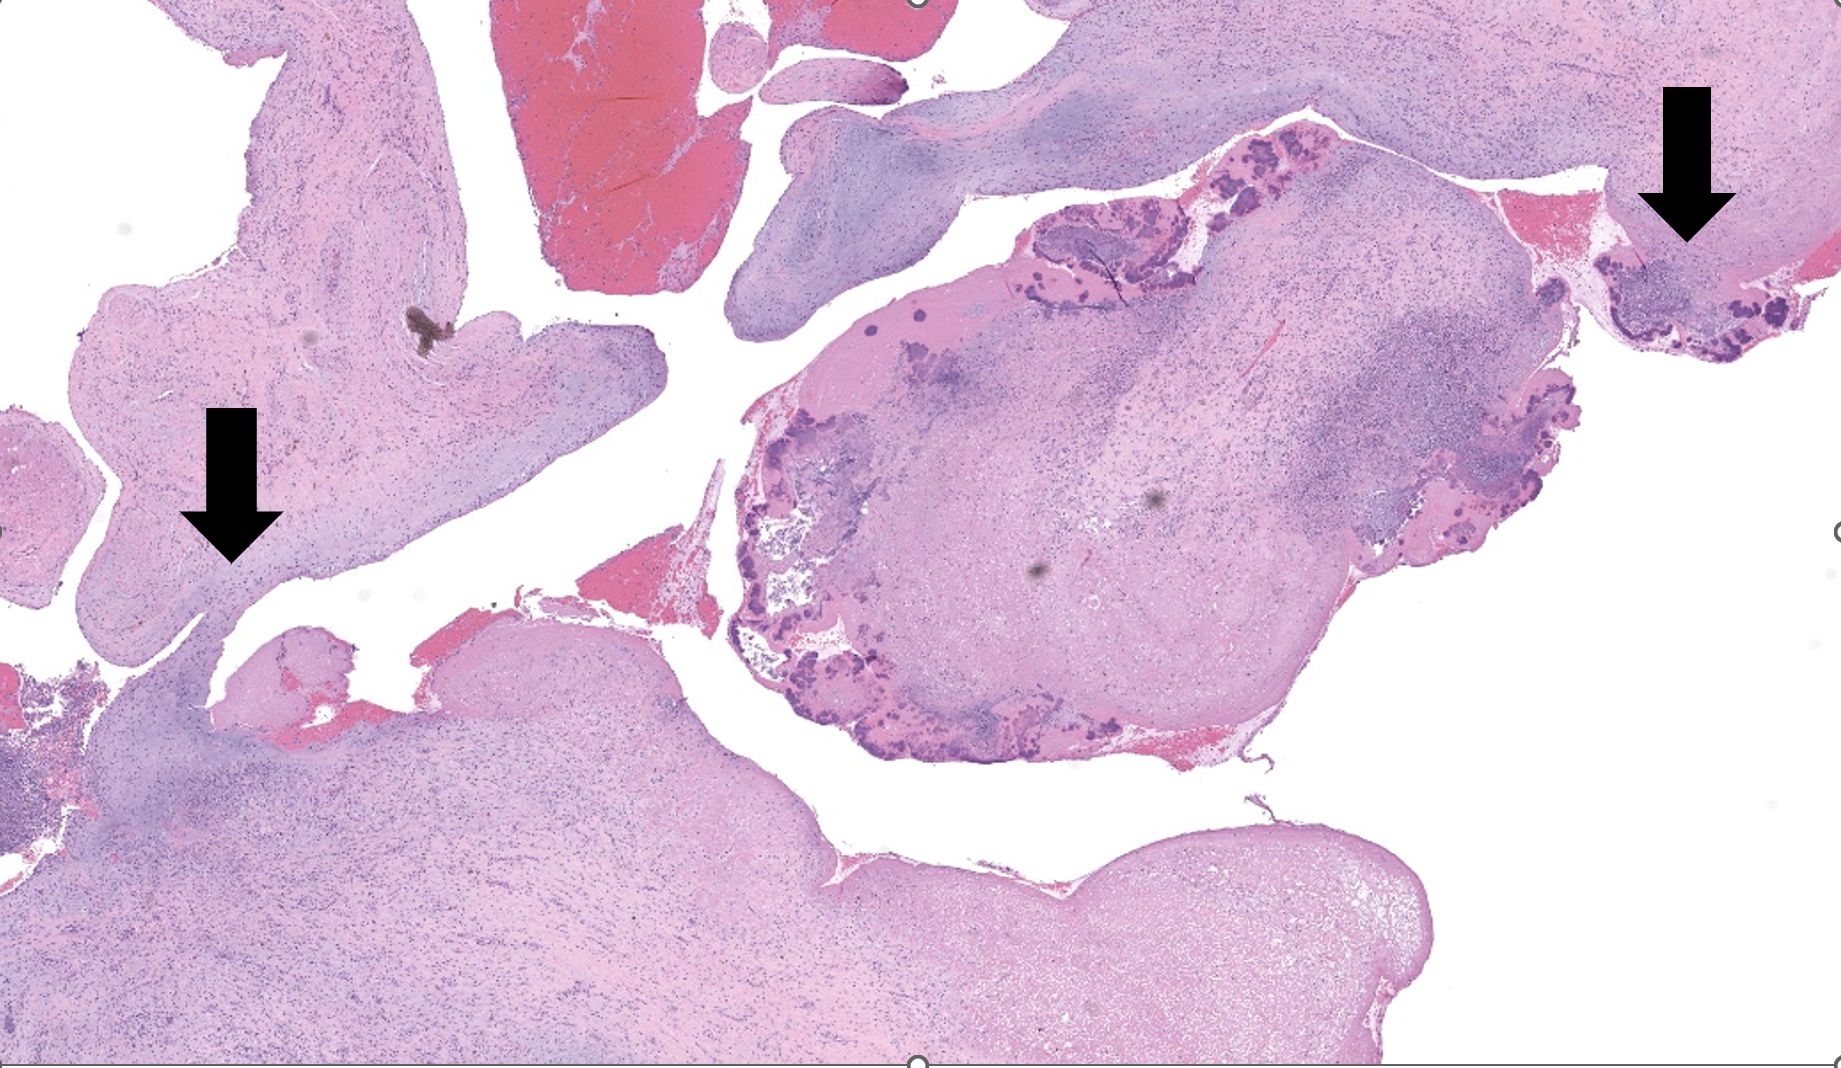

Representative sections of heart and lungs are examined.In the heart, the right atrioventricular valve is extensively overlain by large mats of fibrin, admixed with numerous degenerate and viable neutrophils and multiple coccobacilli bacterial colonies. The valvular stroma is diffusely expanded by moderate myxedema and there are moderate numbers of neutrophils and lesser numbers of hemosiderin-laden macrophages, plasma cells and lymphocytes scattered throughout the valvular stroma and expanding the endocardium of the adjacent papillary muscles. The epicardium and surrounding adipose tissue are mildly infiltrated by small numbers of neutrophils, lymphocytes, and plasma cells.

Heart, right atrioventricular valve: Marked, chronic, fibrinosuppurative valvular endocarditis with intralesional bacterial colonies; Mild, multifocal, suppurative epicarditisLungs: Marked, regional, suppurative, necrotizing embolic pneumonia with vascular thrombosis and intrathrombotic bacteria; Marked, regional, fibrinosuppurative pleuritis

1. Heart, right AV valve: Valvulitis, fibrinosuppurative, chronic, focally extensive, severe, with valvular remodeling and numerous colonies of coccobacilli.